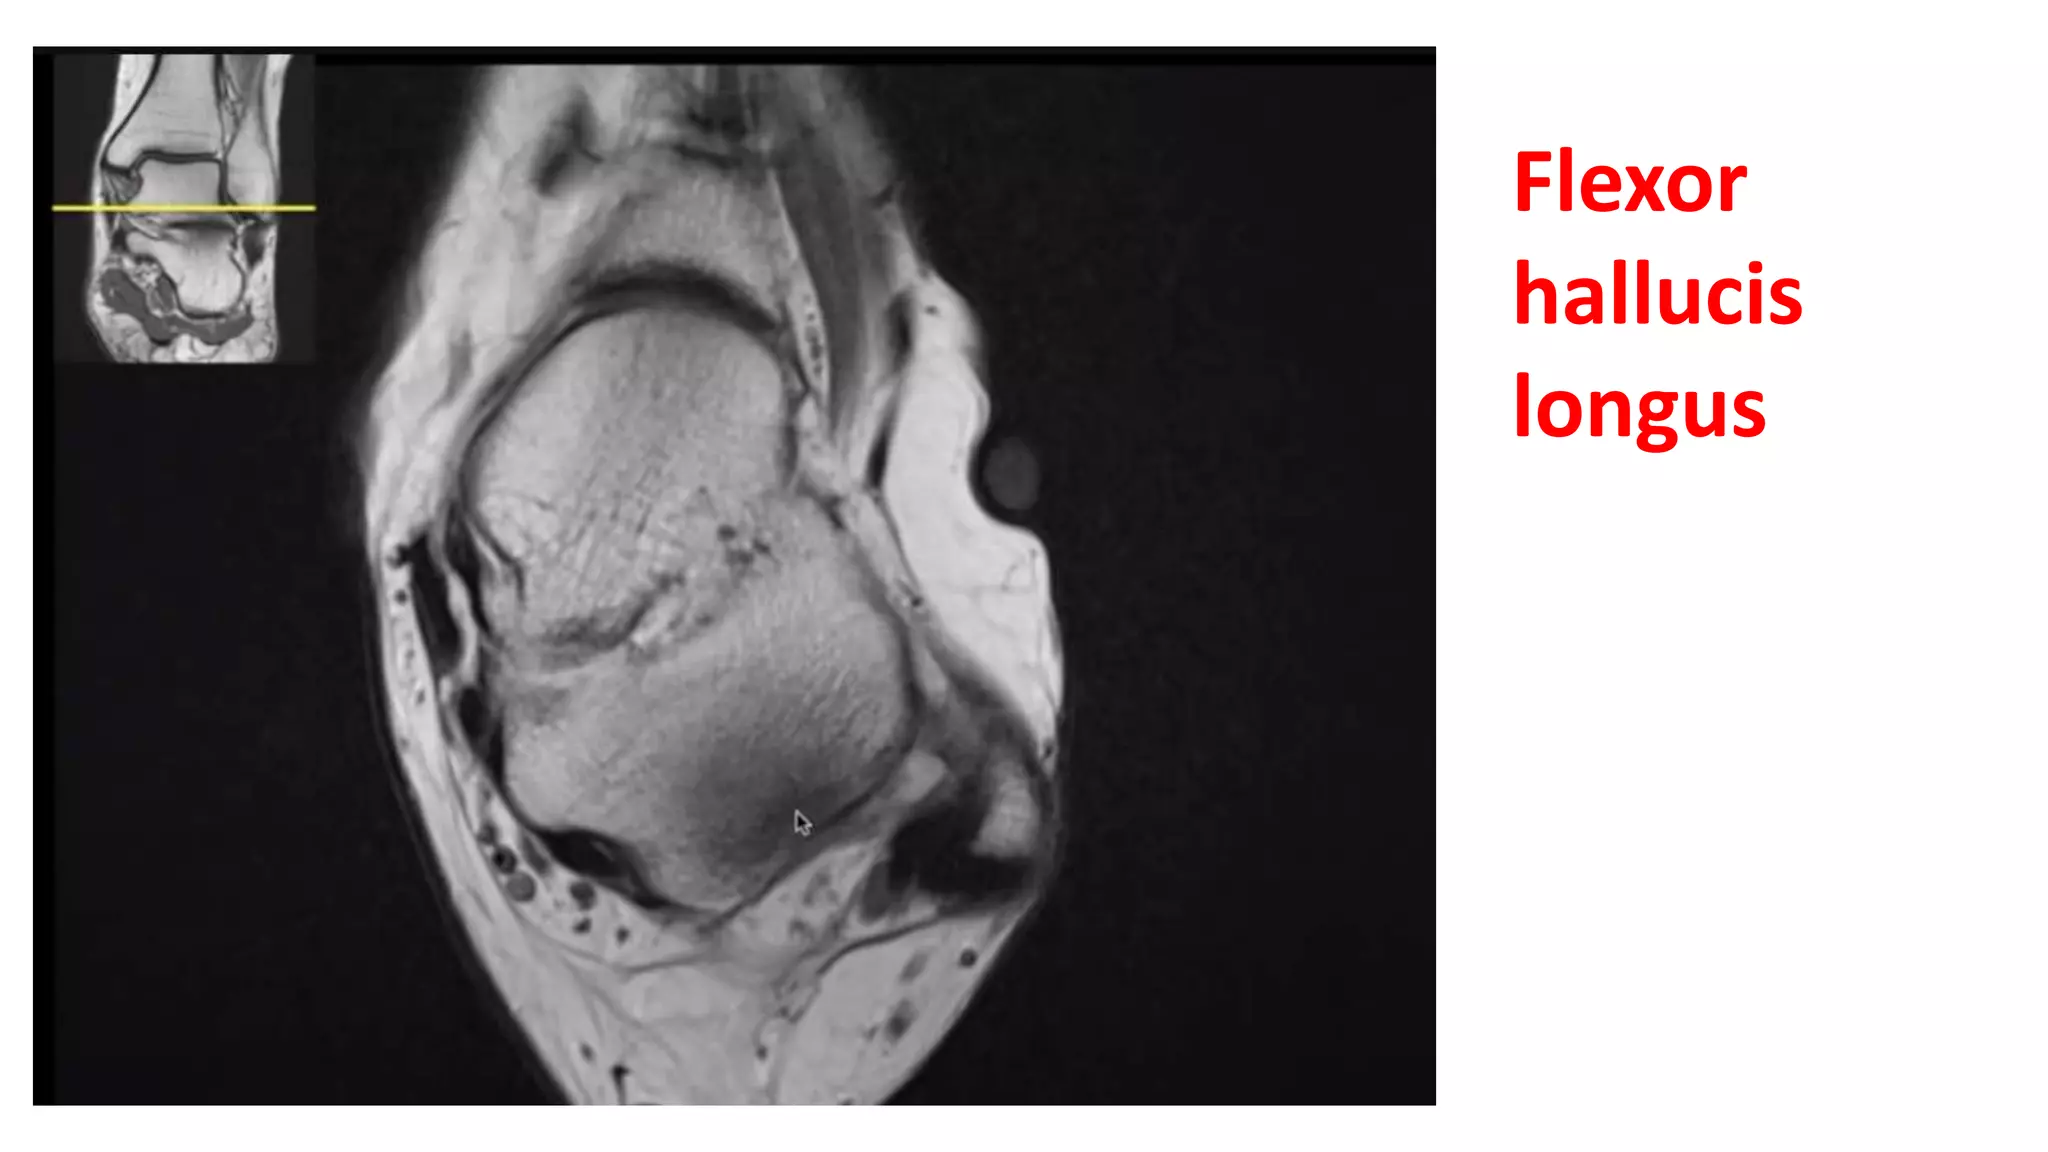

This MRI ankle report describes the anatomy of the ankle, including ligaments such as the anterior and posterior tibiofibular ligaments, syndesmosis ligaments, deltoid ligament, and calcaneofibular ligament. It outlines the tendons in the anterior, lateral, medial, and posterior compartments, including the tibialis posterior, peroneus, flexor hallucis longus, and Achilles tendons. The sinus tarsi is also noted.